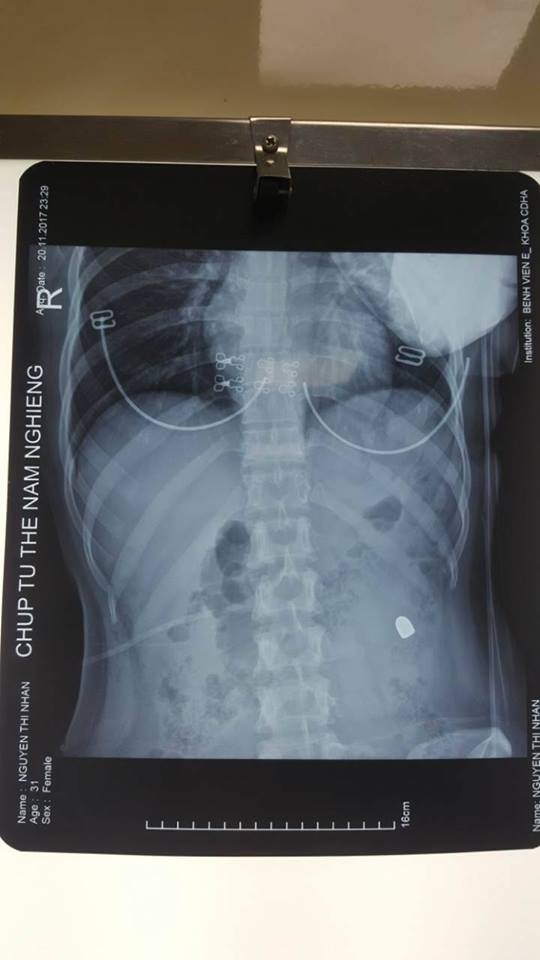

Quan sát vết thương, các bác sĩ nhận thấy vết thương hướng từ phải sang trái, từ phía sau ra phía trước và có thấu bụng (thủng bụng). Kết quả siêu âm cho thấy bệnh nhân có nhiều dịch trong ổ bụng. X-Quang thấy một đầu đạn nằm mạn sườn trái. Các bác sĩ chẩn đoán vết thương thấu bụng nghi ngờ thủng tạng rỗng. Ngay lập tức bệnh nhân này được đưa lên phòng mổ.

| Hình ảnh viên đạn trong vùng bụng bệnh nhân. Ảnh: T.X. |